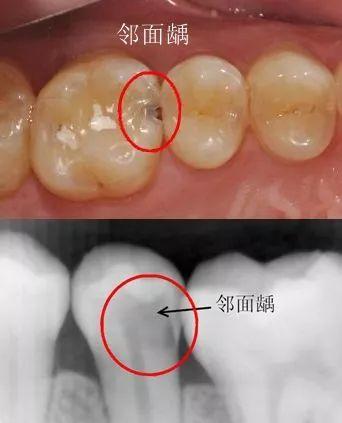

2、坚持用牙线:很多人担心用牙线多了会让牙缝变宽,其实不会的,用牙线能很彻底地清理牙缝里的食物残渣,更有利于防止牙齿邻面长虫牙

牙齿邻面的虫牙很隐蔽,一旦容易发现了大部分已经烂得很大了,一根小小的牙线就能起到很好的预防作用,省钱省力